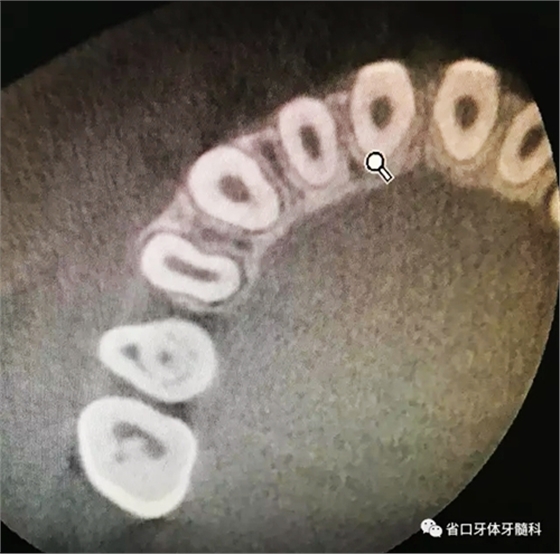

圖3 CBCT(2016-11-13):15由髓腔至根管內(nèi)見團(tuán)塊阻射影像,阻射影中央為透射影,根尖1/3處見根管膨大,腭側(cè)牙槽骨破壞,根尖周低密度影范圍大,上頜竇黏膜增厚。